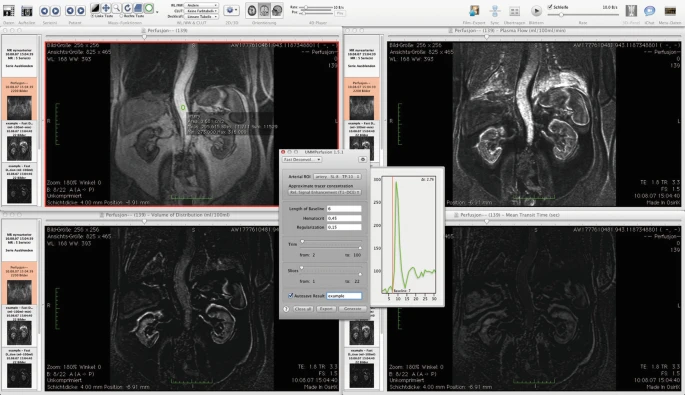

As a result, three new views/viewers are created in which the calculated data are presented. Each viewer shows one parametric map calculated by the deconvolution approach: blood flow (perfusion) in ml/100 ml/min, the blood volume (ml/100 ml) and the mean transit time (s).

- If the autosave function has not been activated before using the generate button, it is still possible to save the results as well as the report after the calculation. In this case, use the export button next to the generate-button.